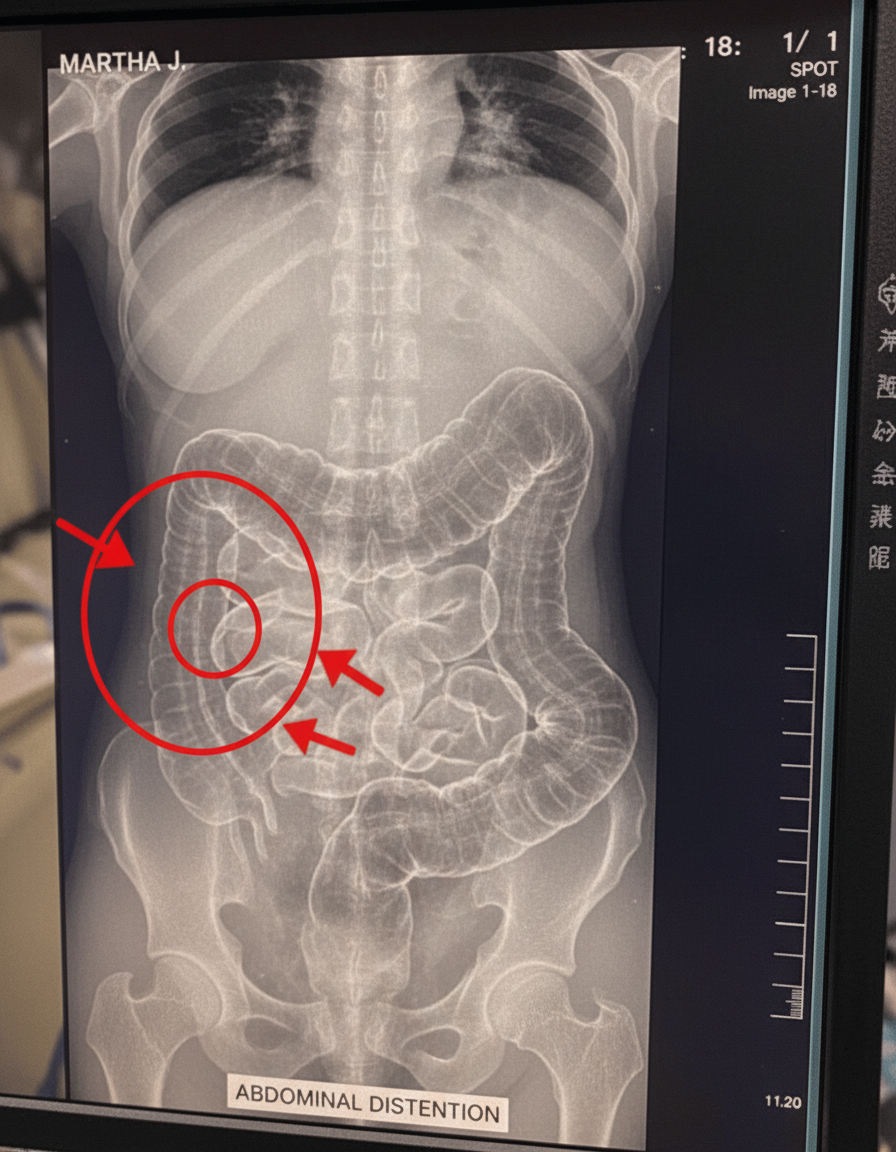

Constipation is classified as “chronic” when an individual experiences fewer than three bowel movements per week over an extended period, typically several weeks to months. This condition affects millions of adults worldwide, making it a surprisingly prevalent health challenge. What many people overlook, however, is the wider impact of prolonged stool retention in the colon. Beyond causing mere bloating, this buildup can exert continuous pressure, affecting the entire gastrointestinal tract. Over time, persistent accumulation may lead to the stretching of the colon, impairing its natural function and making regular elimination even more challenging. Research consistently highlights a link between ongoing constipation and a range of uncomfortable, and potentially serious, health complications if left unaddressed. Proactively recognizing and responding to your body’s early cues is paramount in preventing significant discomfort and more severe health issues.

- **Fecal Impaction/Intestinal Obstruction:** In rare but severe cases, a prolonged buildup of hardened stool can create a complete blockage within the intestine, a condition known as fecal impaction, which necessitates urgent medical intervention.